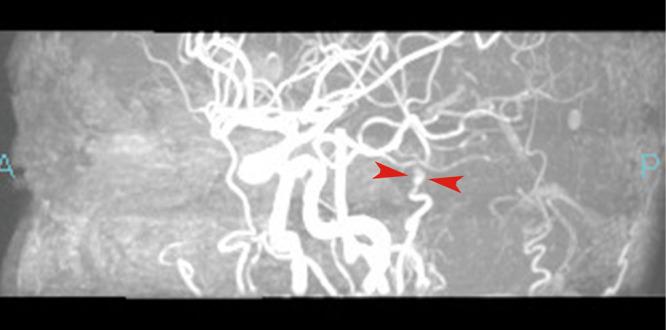

Facial thread-lifting has been popular because of its ease and safety with short down time. However, many physicians perform the procedure in cosmetic clinics, which can result in several complications. This report describes the surgical treatment of iatrogenic superficial temporal artery pseudoaneurysm (STAP) following thread-lifting. A 27-year-old man developed a painless, pulsating soft mass in the pre-auricular region after undergoing a thread-lift in a private cosmetic clinic 3 months before being referred to the authors' hospital. The mass was diagnosed as a STAP, using magnetic resonance imaging. The pseudoaneurysm was resected completely, and the superficial temporal artery was microsurgically reconstructed. Although there are some surgical procedures for treating STAP, such as surgical resection and embolization, the former is considered the first choice. Physicians should be trained before performing thread-lifting and must know the possibility of an iatrogenic STAP appearing after the procedure and the face and neck anatomy to prevent complications.

面部线雕因其操作简便、安全且恢复时间短而广受欢迎。然而,许多医生在美容诊所进行该手术,这可能导致多种并发症。本报告描述了线雕术后医源性颞浅动脉假性动脉瘤(STAP)的手术治疗。一名27岁男性在一家私人美容诊所接受线雕3个月后,于耳前区出现一个无痛性搏动性软肿块,随后被转诊至作者所在医院。通过磁共振成像诊断该肿块为STAP。假性动脉瘤被完全切除,颞浅动脉通过显微外科手术进行了重建。虽然有一些治疗STAP的手术方法,如手术切除和栓塞,但前者被认为是首选。医生在进行线雕前应接受培训,必须了解术后出现医源性STAP的可能性以及面部和颈部解剖结构,以预防并发症。